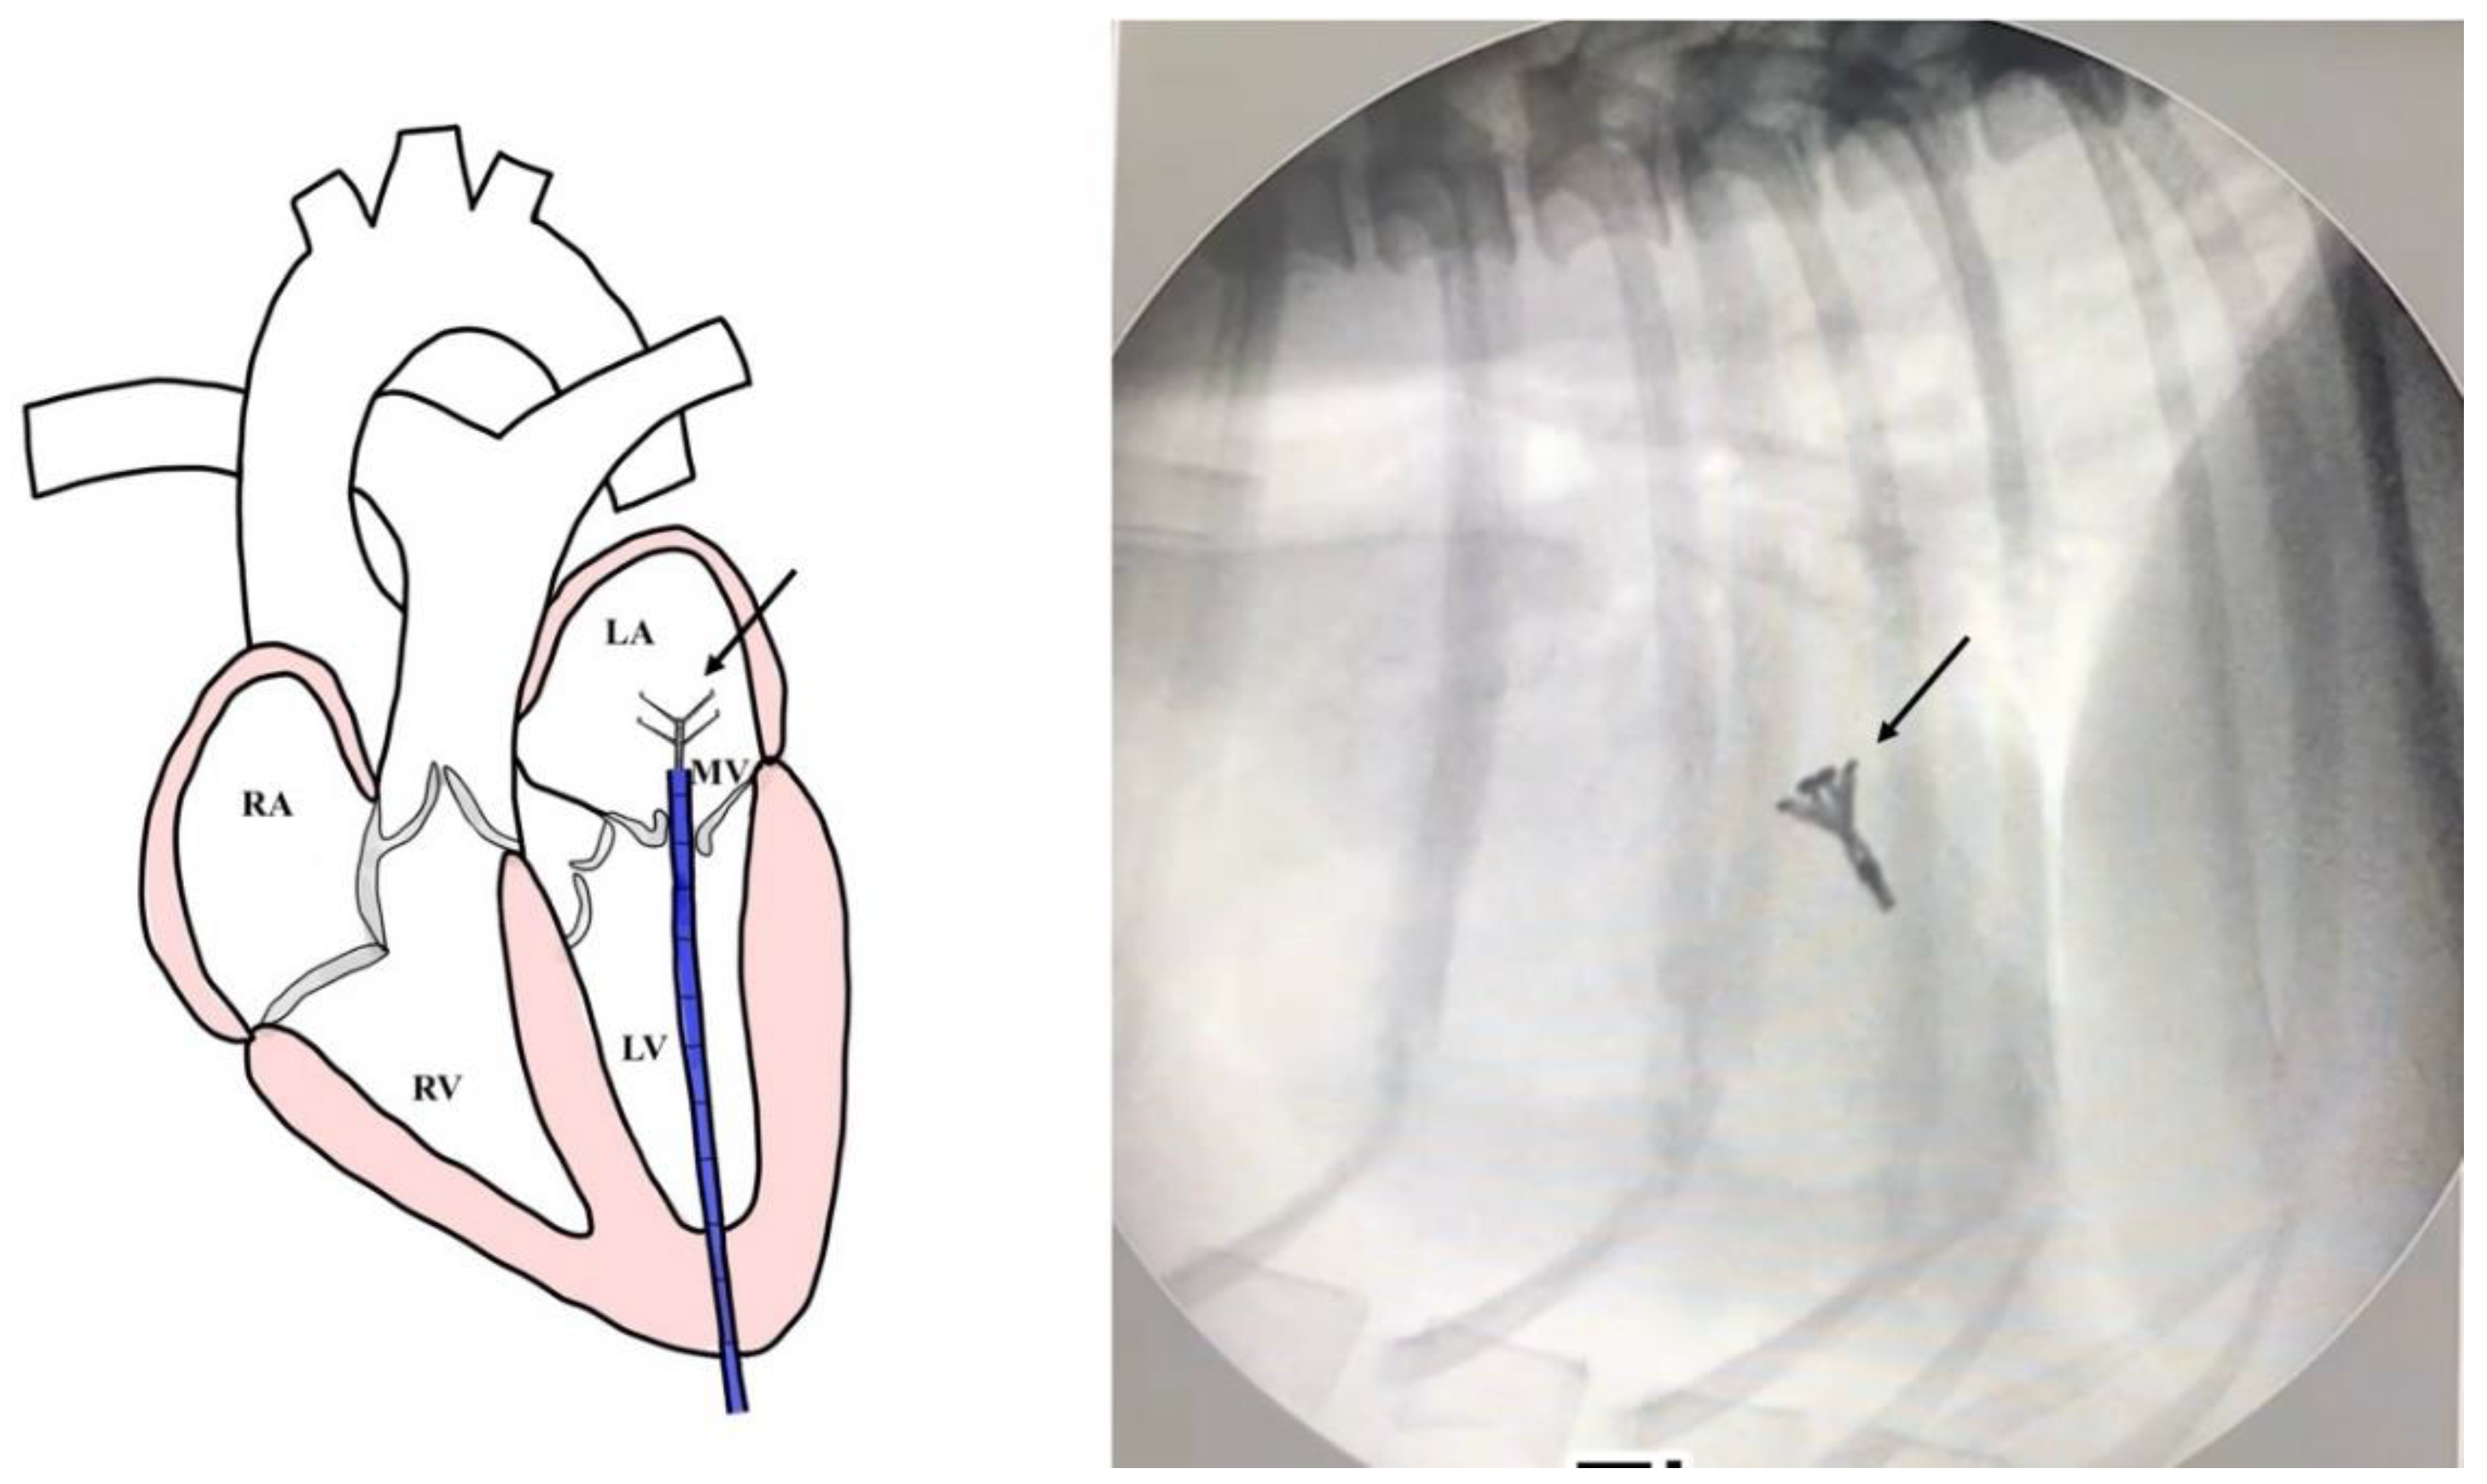

Surgical Intervention